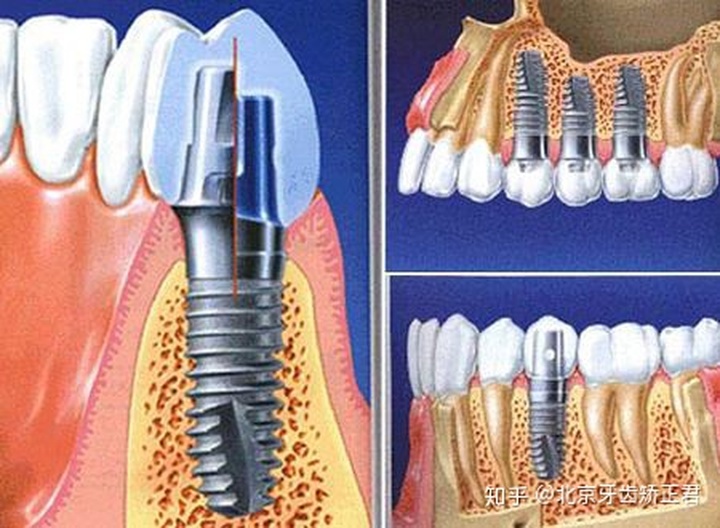

Friadent(费亚丹)种植系统拥有台阶形独有的根形种植体,并有Xive、Frialit、Ankylos等多种种植体可选择,Ankylos是这个系统中更好的一款。Friadent(费亚丹)种植系统在一些骨量轻微不足的病例中可以避免植骨。微锥柱状螺纹种植体设计,可以提高初期稳定性,具有良好的抗旋转性。如果是做单颗牙齿种植,完全可以选择费亚丹种植体系统。

icx的性价比很高,种植体采用四级冷作钛材质,基台是五级钛合金,具有良好的抗压抗裂性。icx表面采用S.L.A大颗粒喷砂+酸蚀处理,保持种植体表面的粗糙度在1-3μm之间,这是非常适合骨结合的范围,所以初期稳定性就很高。同时,icx种植体系统中有一款超亲水性植体,价格比瑞士iti的亲水植体便宜,质量却特别好。icx种植体系统在后磨牙的种植方面很有优势。

贝格bego种植体系统是基于计算机引导下的自动设计和激光定位,使种植牙手术过程由原来的手工操作转化为自动化处理,种植牙过程变得相当精准快捷。贝格bego种植体型号主要是Tipure,Mini,各型号又细分为不同的直径和长度。愈合基台都是钛质的,种植体部分是四级纯钛,表面喷砂工艺,外形有锥形和柱形两种。窄抛光颈部,骨吸收低,初期稳定性好。德国贝格种植体系统在即刻种植技术上有着良好的表现。

camlog种植体采用四级冷作钛材质,强度大,不容易断裂,持久耐用。直径从3.3mm-6.0mm,有五种不同过的型号可以适用于不同的牙槽骨情况。而3.3mm的种植体,即使是牙槽骨只有薄薄的一层也可以成功种植。同时,camlog种植体采用“管槽连接”设计,密合度更好!